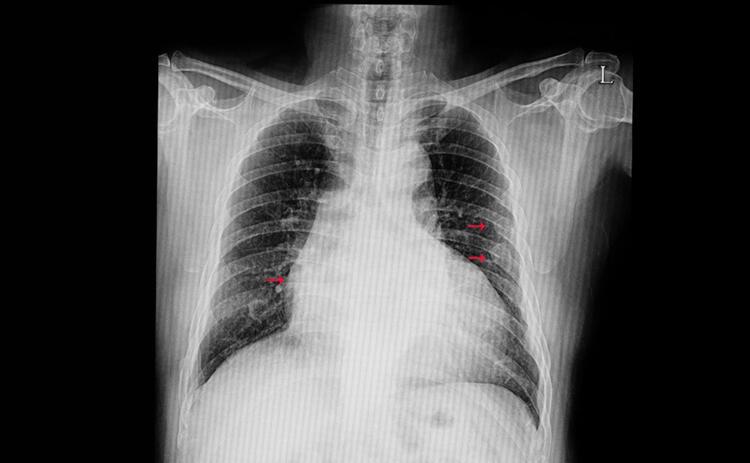

- Akciğer kanseri, dünya çapında yaygın kanser türlerinden biri olarak ön plana çıkıyor. Akciğer kanseri son yıllarda hem gelişmiş hem de gelişmekte olan ülkeler için önemli bir ölüm nedenidir. Tütün ve tütün ürünleri kullanmak akciğer kanserinin en büyük risk faktörlerinden biridir. Akciğer kanseri erken teşhisi için basit bir parmak testini yapabilirsiniz.

- Akciğer kanseri, dünyada en yaygın üçüncü kanserdir ve her geçen yıl hastalık daha yaygın hale geliyor. Her yıl yaklaşık 46.400 kişiye teşhis konuyor. Geçtiğimiz yılın Sağlık Bakanlığı verilerine göre, Türkiye’de yılda ortalama 23 bin erkeğe ve 4 bin 500 kadına akciğer kanseri teşhisi konuluyor.

- AKCİĞER KANSERİ NEDİR? Küçük hücreli olmayan akciğer kanseri (KHDAK) veya küçük hücreli akciğer kanseri (SCLC) olmak üzere iki ana Akciğer kanseri türü vardır. Bazen kanser vücudun başka bir yerinden akciğerlere yayılabilir. Buna akciğer metastazı veya ikincil akciğer kanseri denir. Akciğer kanserinin erken belirtilerini bilmek, riskinizi belirlemenize yardımcı olabilecek Schamroth pencere testi olarak bilinen evde yapılan bir parmak testi ile ortaya çıkabilir.

- Son aşamanın parmakların yumuşak dokularında sıvı toplanması nedeniyle oluştuğu düşünülmektedir. Akciğer kanseri teşhisi için en kısa zamanda doktorunuza başvurun.(Posta)